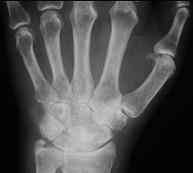

类风湿手X线(如图)的特点是 ( )A、软组织肿胀,关节变形B、关节游离体C、骨质硬化及增生D、骨质疏松E、关节间隙狭窄

问题 类风湿手X线(如图)的特点是 ( )

选项 A、软组织肿胀,关节变形 B、关节游离体 C、骨质硬化及增生 D、骨质疏松 E、关节间隙狭窄

答案 ADE